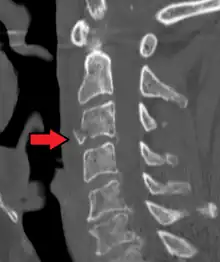

Sagittal reconstruction of a CT scan showing a cervical fracture with dislocation at the level of C6/7